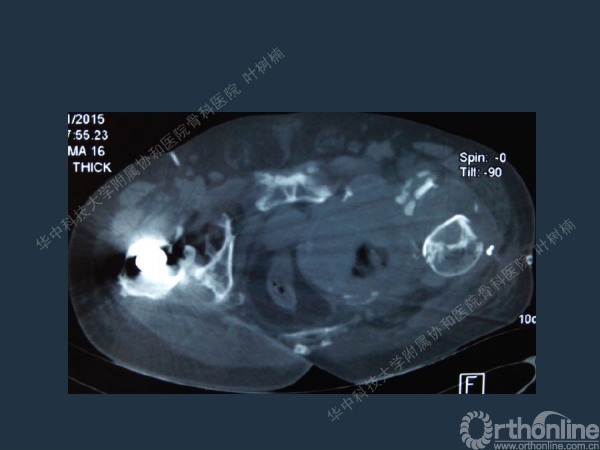

股骨侧翻修

髋臼缺损的处理